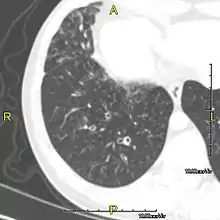

Around 80% of people with primary ciliary dyskinesia experience respiratory problems beginning within a day of birth. Many have a collapsed lobe of the lung and blood oxygen low enough to require treatment with supplemental oxygen.[3] Within the first few months of life, most develop a chronic mucus-producing cough and runny nose.[3] The main consequence of impaired ciliary function is reduced or absent mucus clearance from the lungs, and susceptibility to chronic recurrent respiratory infections, including sinusitis, bronchitis, pneumonia, and otitis media. Progressive damage to the respiratory system is common, including progressive bronchiectasis beginning in early childhood, and sinus disease (sometimes becoming severe in adults). However, diagnosis is often missed early in life despite the characteristic signs and symptoms.[4] In males, immotility of sperm can lead to infertility, although conception remains possible through the use of in vitro fertilization, there also are reported cases where sperm were able to move.[5] Trials have also shown that there is a marked reduction in fertility in females with Kartagener's syndrome due to dysfunction of the oviductal cilia.[6]

Many affected individuals experience hearing loss and show symptoms of otitis media which demonstrates variable responsiveness to the insertion of myringotomy tubes or grommets. Some patients have a poor sense of smell, which is believed to accompany high mucus production in the sinuses (although others report normal – or even acute – sensitivity to smell and taste). Clinical progression of the disease is variable, with lung transplantation required in severe cases. Susceptibility to infections can be drastically reduced by an early diagnosis. Treatment with various chest physiotherapy techniques has been observed to reduce the incidence of lung infection and to slow the progression of bronchiectasis dramatically. Aggressive treatment of sinus disease beginning at an early age is believed to slow long-term sinus damage (although this has not yet been adequately documented). Aggressive measures to enhance clearance of mucus, prevent respiratory infections, and treat bacterial superinfections have been observed to slow lung-disease progression. The predicted incidence is 1 in approximately 7500.[7]

Several diagnostic tests for this condition have been proposed.[16] These include nasal nitric oxide levels as a screening test, light microscopy of biopsies for ciliary beat pattern and frequency and electron microscopic examination of dynein arms, as the definite diagnosis method. Genetic testing has also been proposed but this is difficult given that there are multiple genes involved.